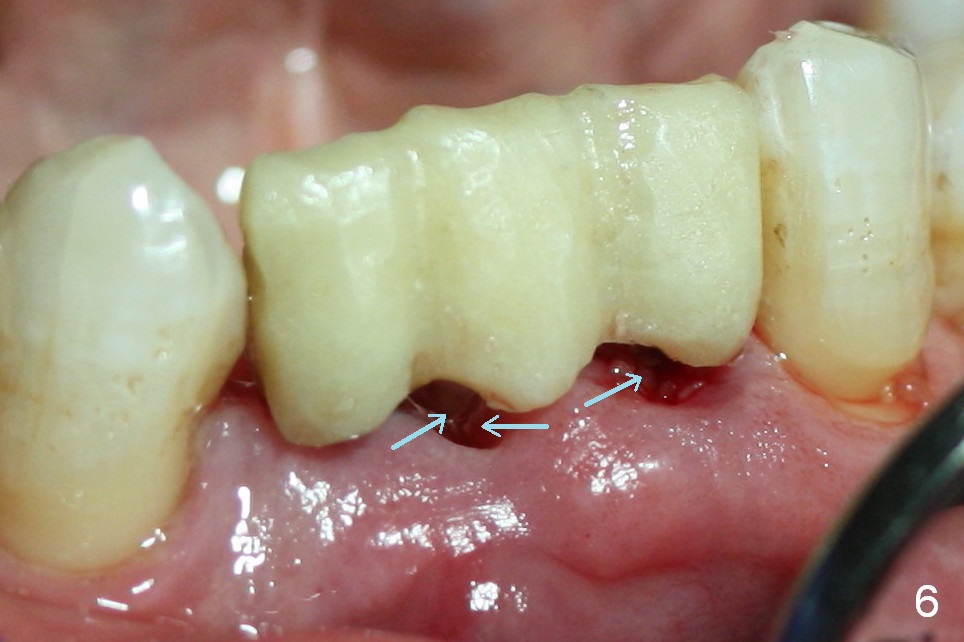

The teeth give the gingiva scallop shaped (Fig.1, 2). The scallop is less where the tooth is absent (Fig.2 *). The scallop must have been distinct when the tooth is just extracted with prominent papillae (Fig.2,3 ^).

One of the functions of an immediate provisional is to maintain and create the valleys and peaks of the gingival morphology (Fig.4-6). When the wound heals initially, the provisional should be modified (Fig.5 yellow curves) to push the gingiva aside (Fig.6 arrows) to create oval pontic and papillae (Fig.5).